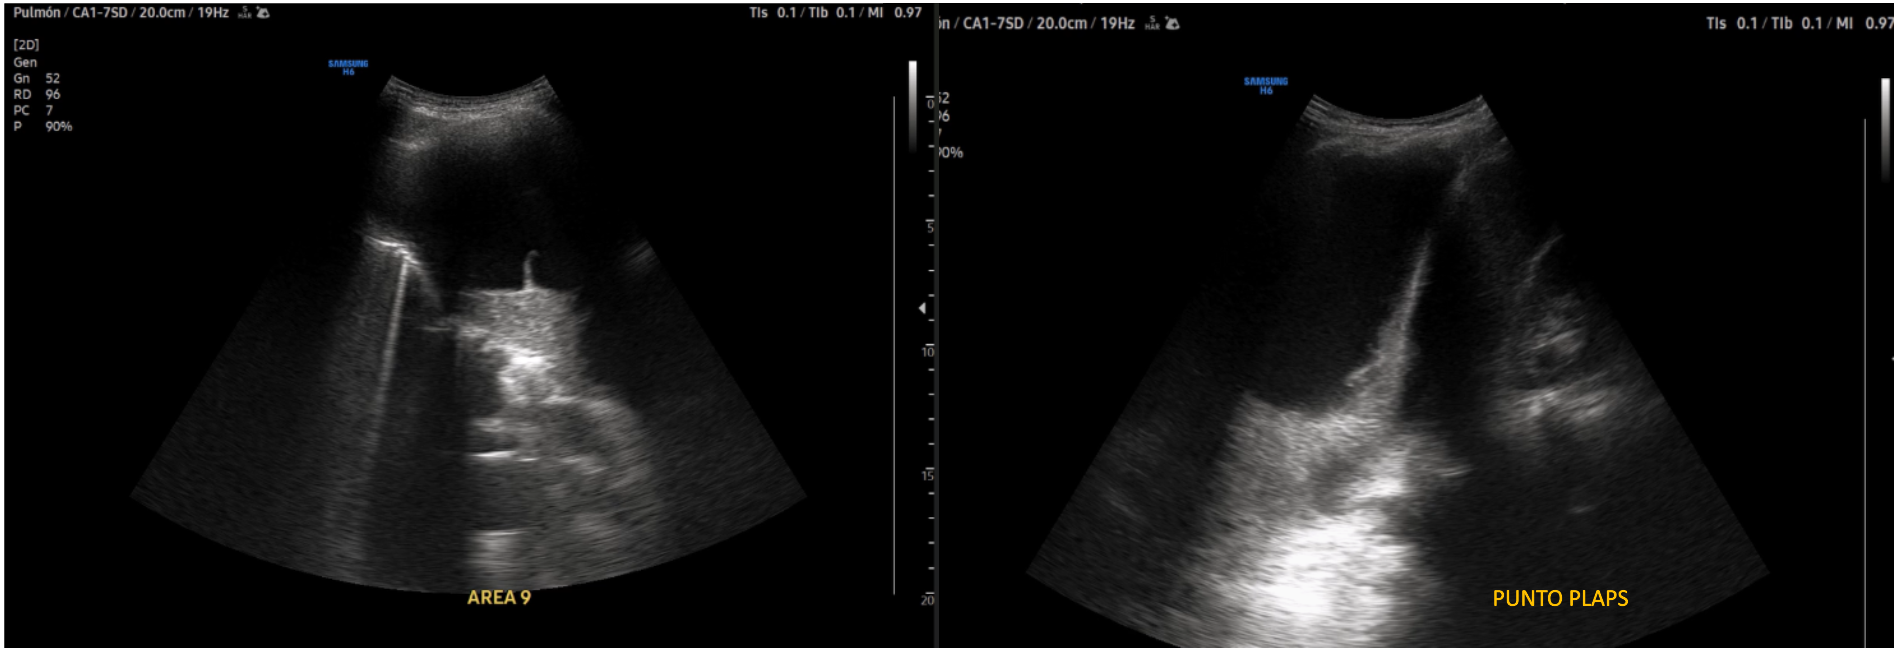

Realizamos Ecografía clínica pulmonar: imagen anecoica con septos finos y signo de la medusa compatible con derrame pleural tabicado con atelectasia en base derecha de aproximadamente 1150 ml por cuantificación de Goecke 2, en ápex líneas B finas. Campo pulmonar izquierdo líneas A.

Múltiples toracocentesis diagnósticas/evacuadoras total de 1,08 litros y con líquido pleural tipo exudado linfocítico; microbiología y citología negativa. Ecografía pulmonar control: persistencia de DP y aumento de tabicación. Tomografía abdomino pélvico confirma persistencia de derrame. Analítica destaca PCR y Procalcitonina elevadas. Nueva toraconcentésis ecodirigida: líquido pútrido, cultivo de DP: positiva para Parvimonas micra Fusobacterium nucleatum. Antígeno orina positivo: neumococo. Inicia Piperacilina/Tazobactam e inserción drenaje pleural con aspiración e instilación de urokinasa durante 10 días.